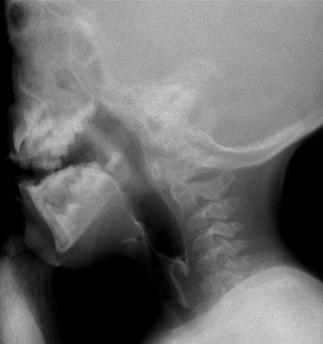

Videofluoroscopy